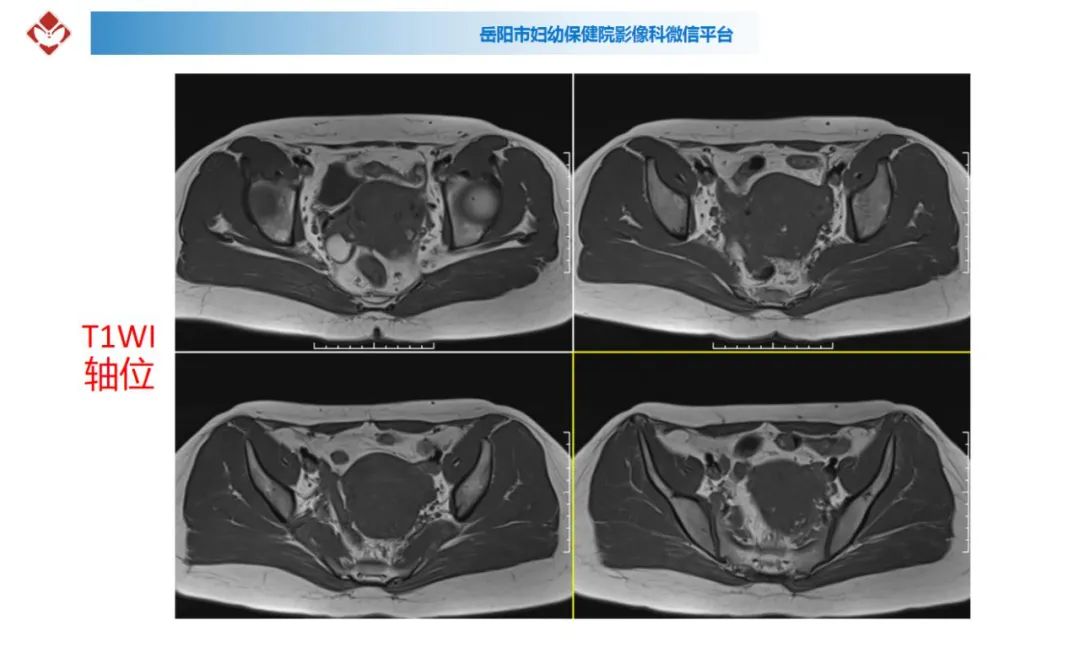

典型疑难病例讨论

来源:岳阳市妇幼保健院影像科